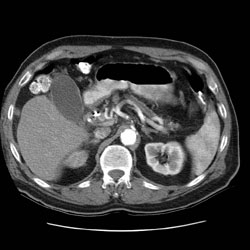

RADIOLOGY: PANCREAS: Case# 33693: ADENOCARCINOMA OF THE PANCREATIC HEAD. DIVERTICULOSIS. The patient is a 75 year old male with common bile duct stenosis and painless jaundice. Examination is requested to evaluate for a pancreatic mass. Prominence of the pancreatic head with atrophy of and pancreatic duct dilatation within the body and tail. These findings are consistent with adenocarcinoma of the pancreatic head. In addition the SMV appears encased in the region of the pancreatic head. 2. 1.2 x 1 cm lymph node seen just superior to the pancreatic neck which may represent metastatic disease. No other evidence for lymphadenopathy is identified. 3. Status post internal/external biliary drainage catheter. 4. Diverticulosis.